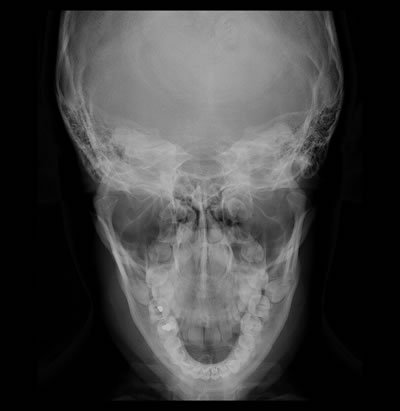

Póstero-Anterior (PA) De Mandíbula